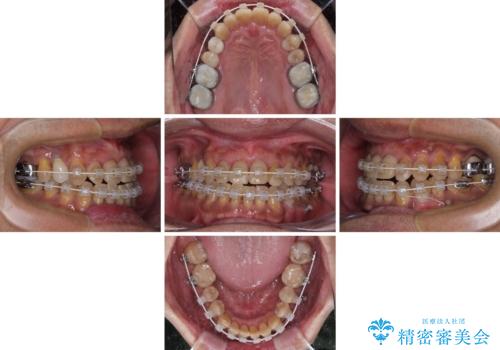

- 矯正装置

- 審美装置

- 1年10ヶ月

- 前歯のクロスバイトを気にして来院された患者様です。

下顎骨の左右のずれがあり、下顎全体が前方に出ている状態であったので、無理をせずにワイヤー装置にて矯正治療を行うこととしました。

クロスバイト改善には難儀しましたが、咬みやすく、笑ったときに清潔感ある口元に仕上げることができました。